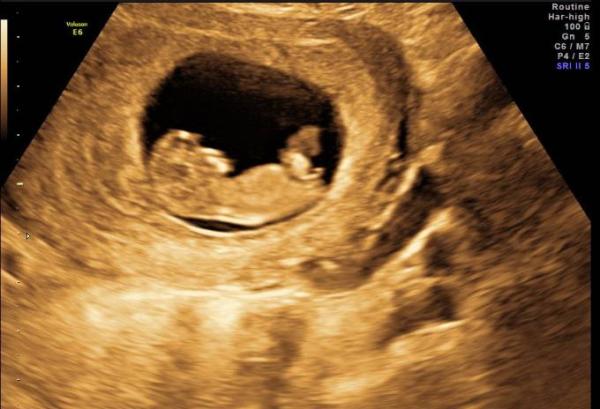

Nee, tut mir leid, aber da erkenne ich nichts. Ich kann dir ja mal ein "optimales" Bild von mir zeigen. Allerdings war das auch in der 10. Ssw und deswegen leider noch nicht aussagekräftig. Aber bei mir würde ich, wenn es später noch so aussieht, Mädchen sagen, wei diese Noppe parallel zur Wirbelsäule verläuft. Irgendwie wirkt es schärfer als bei deinem Bild. LG

Bild zu